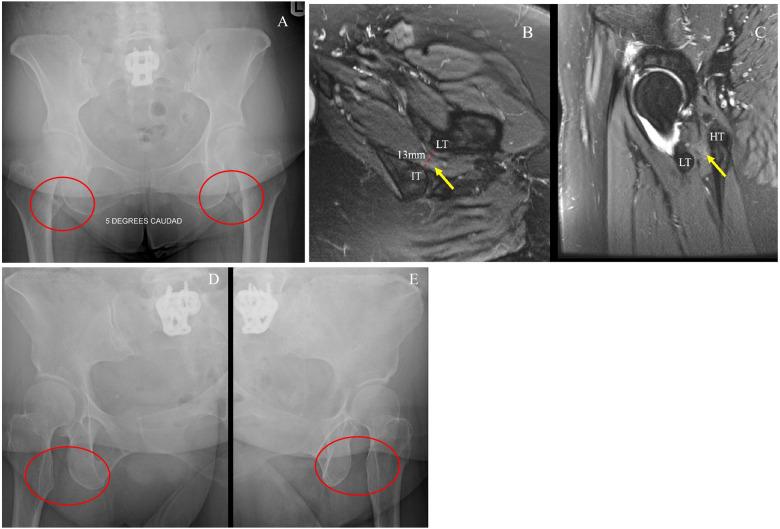

Hip-spine syndrome: rationale for ischiofemoral impingement, femoroacetabular impingement and abnormal femoral torsion leading to low back pain.

The term 'hip-spine syndrome' was introduced in recognition of the frequent occurrence of concomitant symptoms at the hip and lumbar spine. Limitations in hip range of motion can result in abnormal lumbopelvic mechanics. Ischiofemoral impingement, femoroacetabular impingement and abnormal femoral torsion are increasingly linked to abnormal hip and spinopelvic biomechanics. The purpose of this narrative review is to explain the mechanism by which these three abnormal hip pathologies contribute to increased low back pain in patients without hip osteoarthritis. This paper presents a thorough rationale of the anatomical and biomechanical characteristics of the aforementioned hip pathologies, and how each contributes to premature coupling and limited hip flexion/extension. The future of hip and spine conservative and surgical management requires the implementation of a global hip-spine-pelvis-core approach to improve patient function and satisfaction.